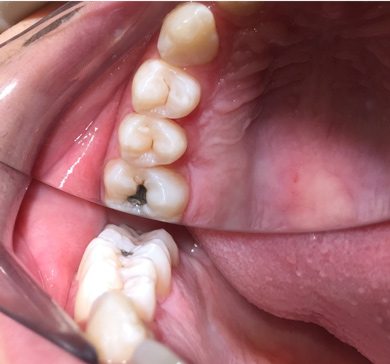

Fig 12.  After the rubber dam is removed, the procedure is complete.

Figure 12

20. Remove the rubber dam, and the procedure is complete (Figure 12).

A 28-year-old woman, who previously had braces, had circumferential gumline decalcification (Figure 1) and wished to arrest lesions before they worsened (bitewing, Figure 2). The following protocol is consistent with the product instructions for the resin infiltration material from DMG America, which is the only commercially available resin infiltration system in the US.